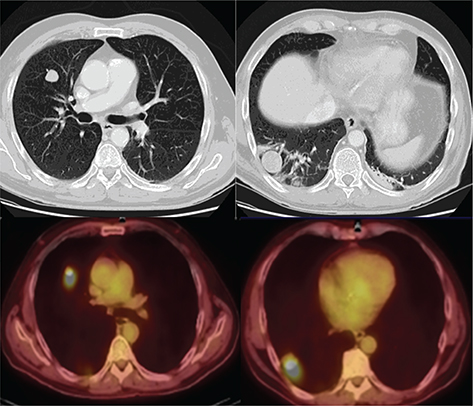

Fig 4

Figure 4. Lymph nodes. FDG PET/CT demonstrates hypermetabolic activity within left supraclavicular (thick solid arrow) and periaortic lymph nodes (thick open arrow). This patient was undergoing restaging for a history of seminoma. Findings on PET/CT were consistent with retroperitoneal and left supraclavicular nodal disease.